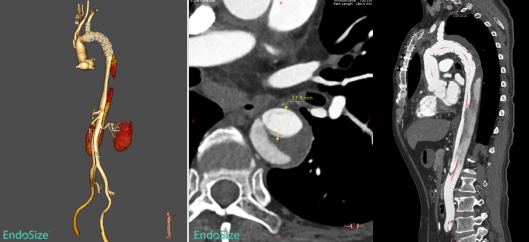

术后复查CTA进一步证实,患者残余夹层覆膜支架段内膜破口有效覆盖,假腔无血流,远端真腔扩张良好。

术后复查的CTA